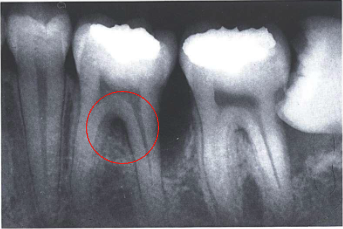

describe what’s being circled

vertical bone loss: furcation involvement